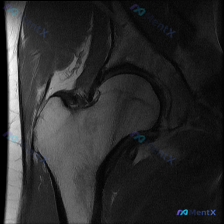

看到一份髋部MRI(T1序列-冠状位)的影像分析,患者可能有髋部疼痛,临床怀疑盂唇病变。 先看影像评估要点: 1. 单序列T1对盂唇病变识别力弱,只能看黄骨髓信号和解剖结构 2. 目前影像上股骨头轮廓圆整,骨髓信号均匀,关节间隙无明显狭窄 3. 盂唇区域未看到明确的信号增高或形态不连续(T1上正常盂...

看到一份有意思的病例资料:患者临床怀疑盂唇病变,但仅提供了髋关节MRI-T2序列冠状位单幅图像。影像分析显示: - 股骨头与髋臼对合关系大致正常,无明显半脱位 - 骨髓信号均匀,无水肿或坏死征象 - 盂唇信号连续,未见明显撕裂或囊变 - 软骨及周围软组织无异常 - 关节腔无积液 这份资料里有几个关键...

看到一份髋关节MRI的影像分析材料,原假设是盂唇病变,但提供的T1矢状位图像上没有发现明确的损伤征象。先放第一部分影像发现,大家第一反应怎么看?

最近看到一个髋关节MRI的病例,患者有腹股沟疼痛,但T1矢状位图像显示盂唇形态正常、信号均匀,无明确撕裂征象。这个病例的矛盾点在于临床症状和影像表现不一致,大家觉得可能是什么原因呢? 先放一下影像学分析的重点: - 矢状位T1图像显示髋臼与股骨头解剖关系正常 - 股骨头形态圆滑,无塌陷、变扁 - 关...